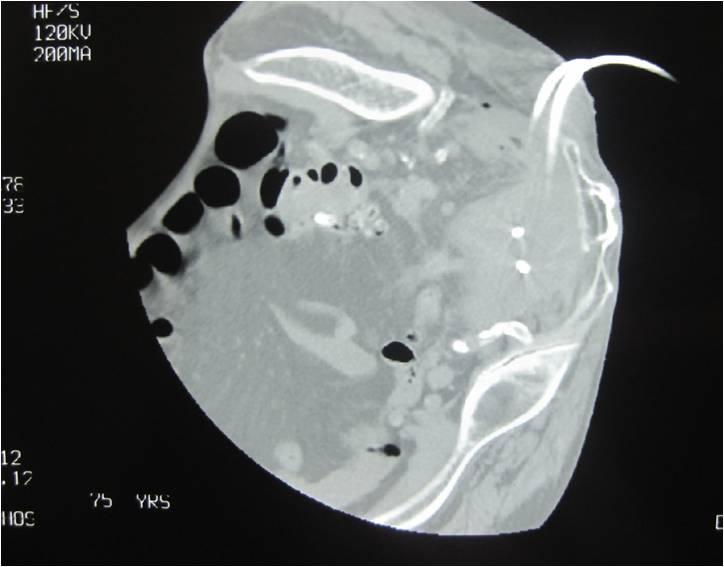

- Placement of two sump catheters in a abdominal abscess (surgery of inflammatory bowel disease), displacement of upper one